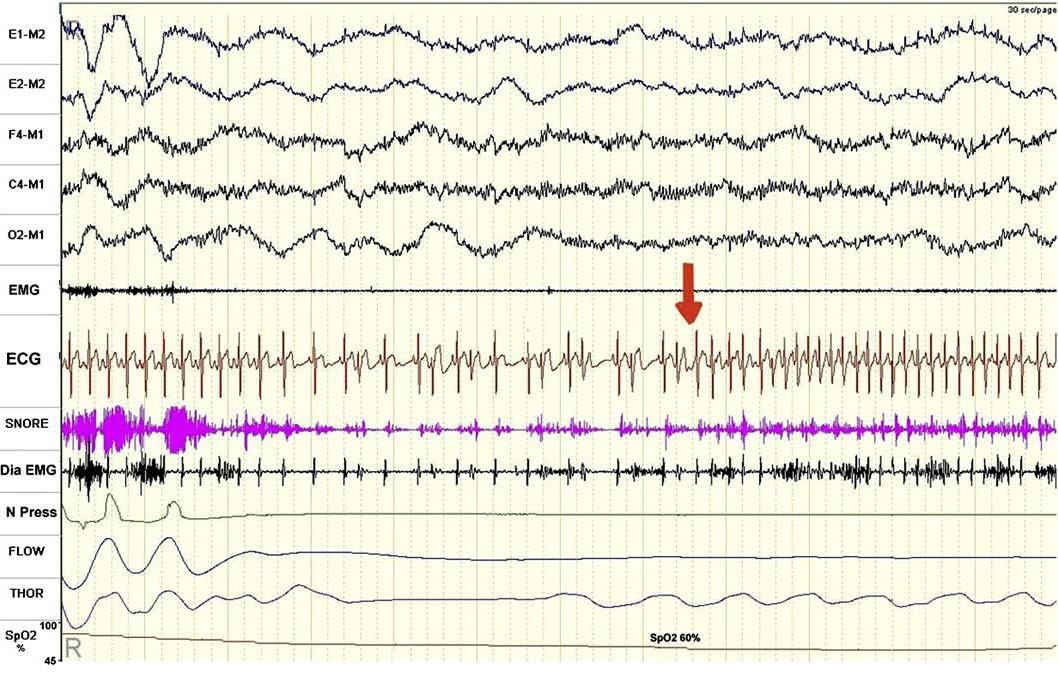

VPC, tachycardia in OSA pt

After CPAP